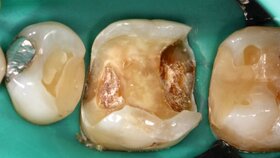

Um den tatsächlichen Zustand der Pulpa zu beurteilen, muss man unter wissenschaftlichen Aspekten histologische Studien durchführen. Nur so können wir Sicherheit über das Behandlungsergebnis bekommen. Alle mir bekannten und in meinem Artikel zitierten histologischen Studien kommen zu dem eindeutigen Schluss, dass das Belassen von Karies über kurz oder lang zu einer irreversiblen Pulpitis führt [Dammaschke, 2025]. Diese Ergebnisse stützen sich dabei nicht nur auf zwölf Zähne der Studie von Ricucci et al. [2020]. Es gibt im Umkehrschluss bisher keine einzige Studie, die nachweisen konnte, dass die selektive Kariesexkavation NICHT zu pulpitischen Veränderungen führt. Solche histologischen Studien am Menschen durchzuführen, ist aber aufwändig und sie müssen auch immer unter einem ethischen Aspekt betrachtet werden, da die Zähne hierzu unweigerlich extrahiert werden müssen. Die Anzahl solcher Studien ist daher leider limitiert und wird es auch bleiben.

Sie geben zu Recht an, dass die Patienten nach selektiver Kariesexkavation klinisch zu einem Großteil beschwerdefrei sind. Nur kann eine Beschwerdefreiheit unter medizinischen Aspekten nicht bedeuten, dass kein Behandlungsbedarf besteht. Typische Beispiele in der Zahnmedizin sind die Gingivitis und Parodontitis. Auch eine periapikale Parodontitis muss nicht zwingend mit Beschwerden verbunden sein. Lässt man sie daher unbehandelt? Denkt man an die Humanmedizin, könnte man etwas überspitzt formulieren, dass auch ein Bluthochdruck oder eine Diabetes nicht behandlungsbedürftig seien, da diese Erkrankungen, zumindest im Anfangsstadium, keine klinischen Beschwerden verursachen. Die bei einer Vorsorgekoloskopie entdeckten Adenome müssten logischerweise dann auch nicht entfernt werden, da sie ja nicht wehtun. Wir wissen aber auch aus histologischen Studien, dass Adenome Vorstufen für Karzinomerkrankungen sein können.

Nochmal: Beschwerdefreiheit bedeutet eben nicht, dass ein Gewebe gesund ist und folglich die Therapie erfolgreich war. Denn beschwerdefreie Patienten können eine „ongoing“ chronische Entzündung haben, die ihnen schadet.